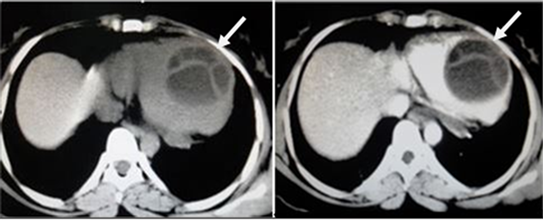

Figure 10. Class CE2 hydatid cyst in myocardium of ventricle in a 25 yr female patient with history of chest pain. Pain and CECT chest showed well defined, thin walled cystic lesion with internal loculations with “rosette-like appearance” with no enhancement on post contrast in myocardium of ventricle.